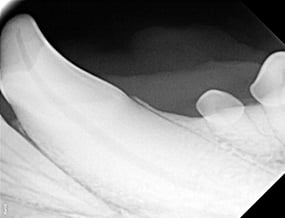

Below: Radiograph of CCF - crown, before RCT and restoration